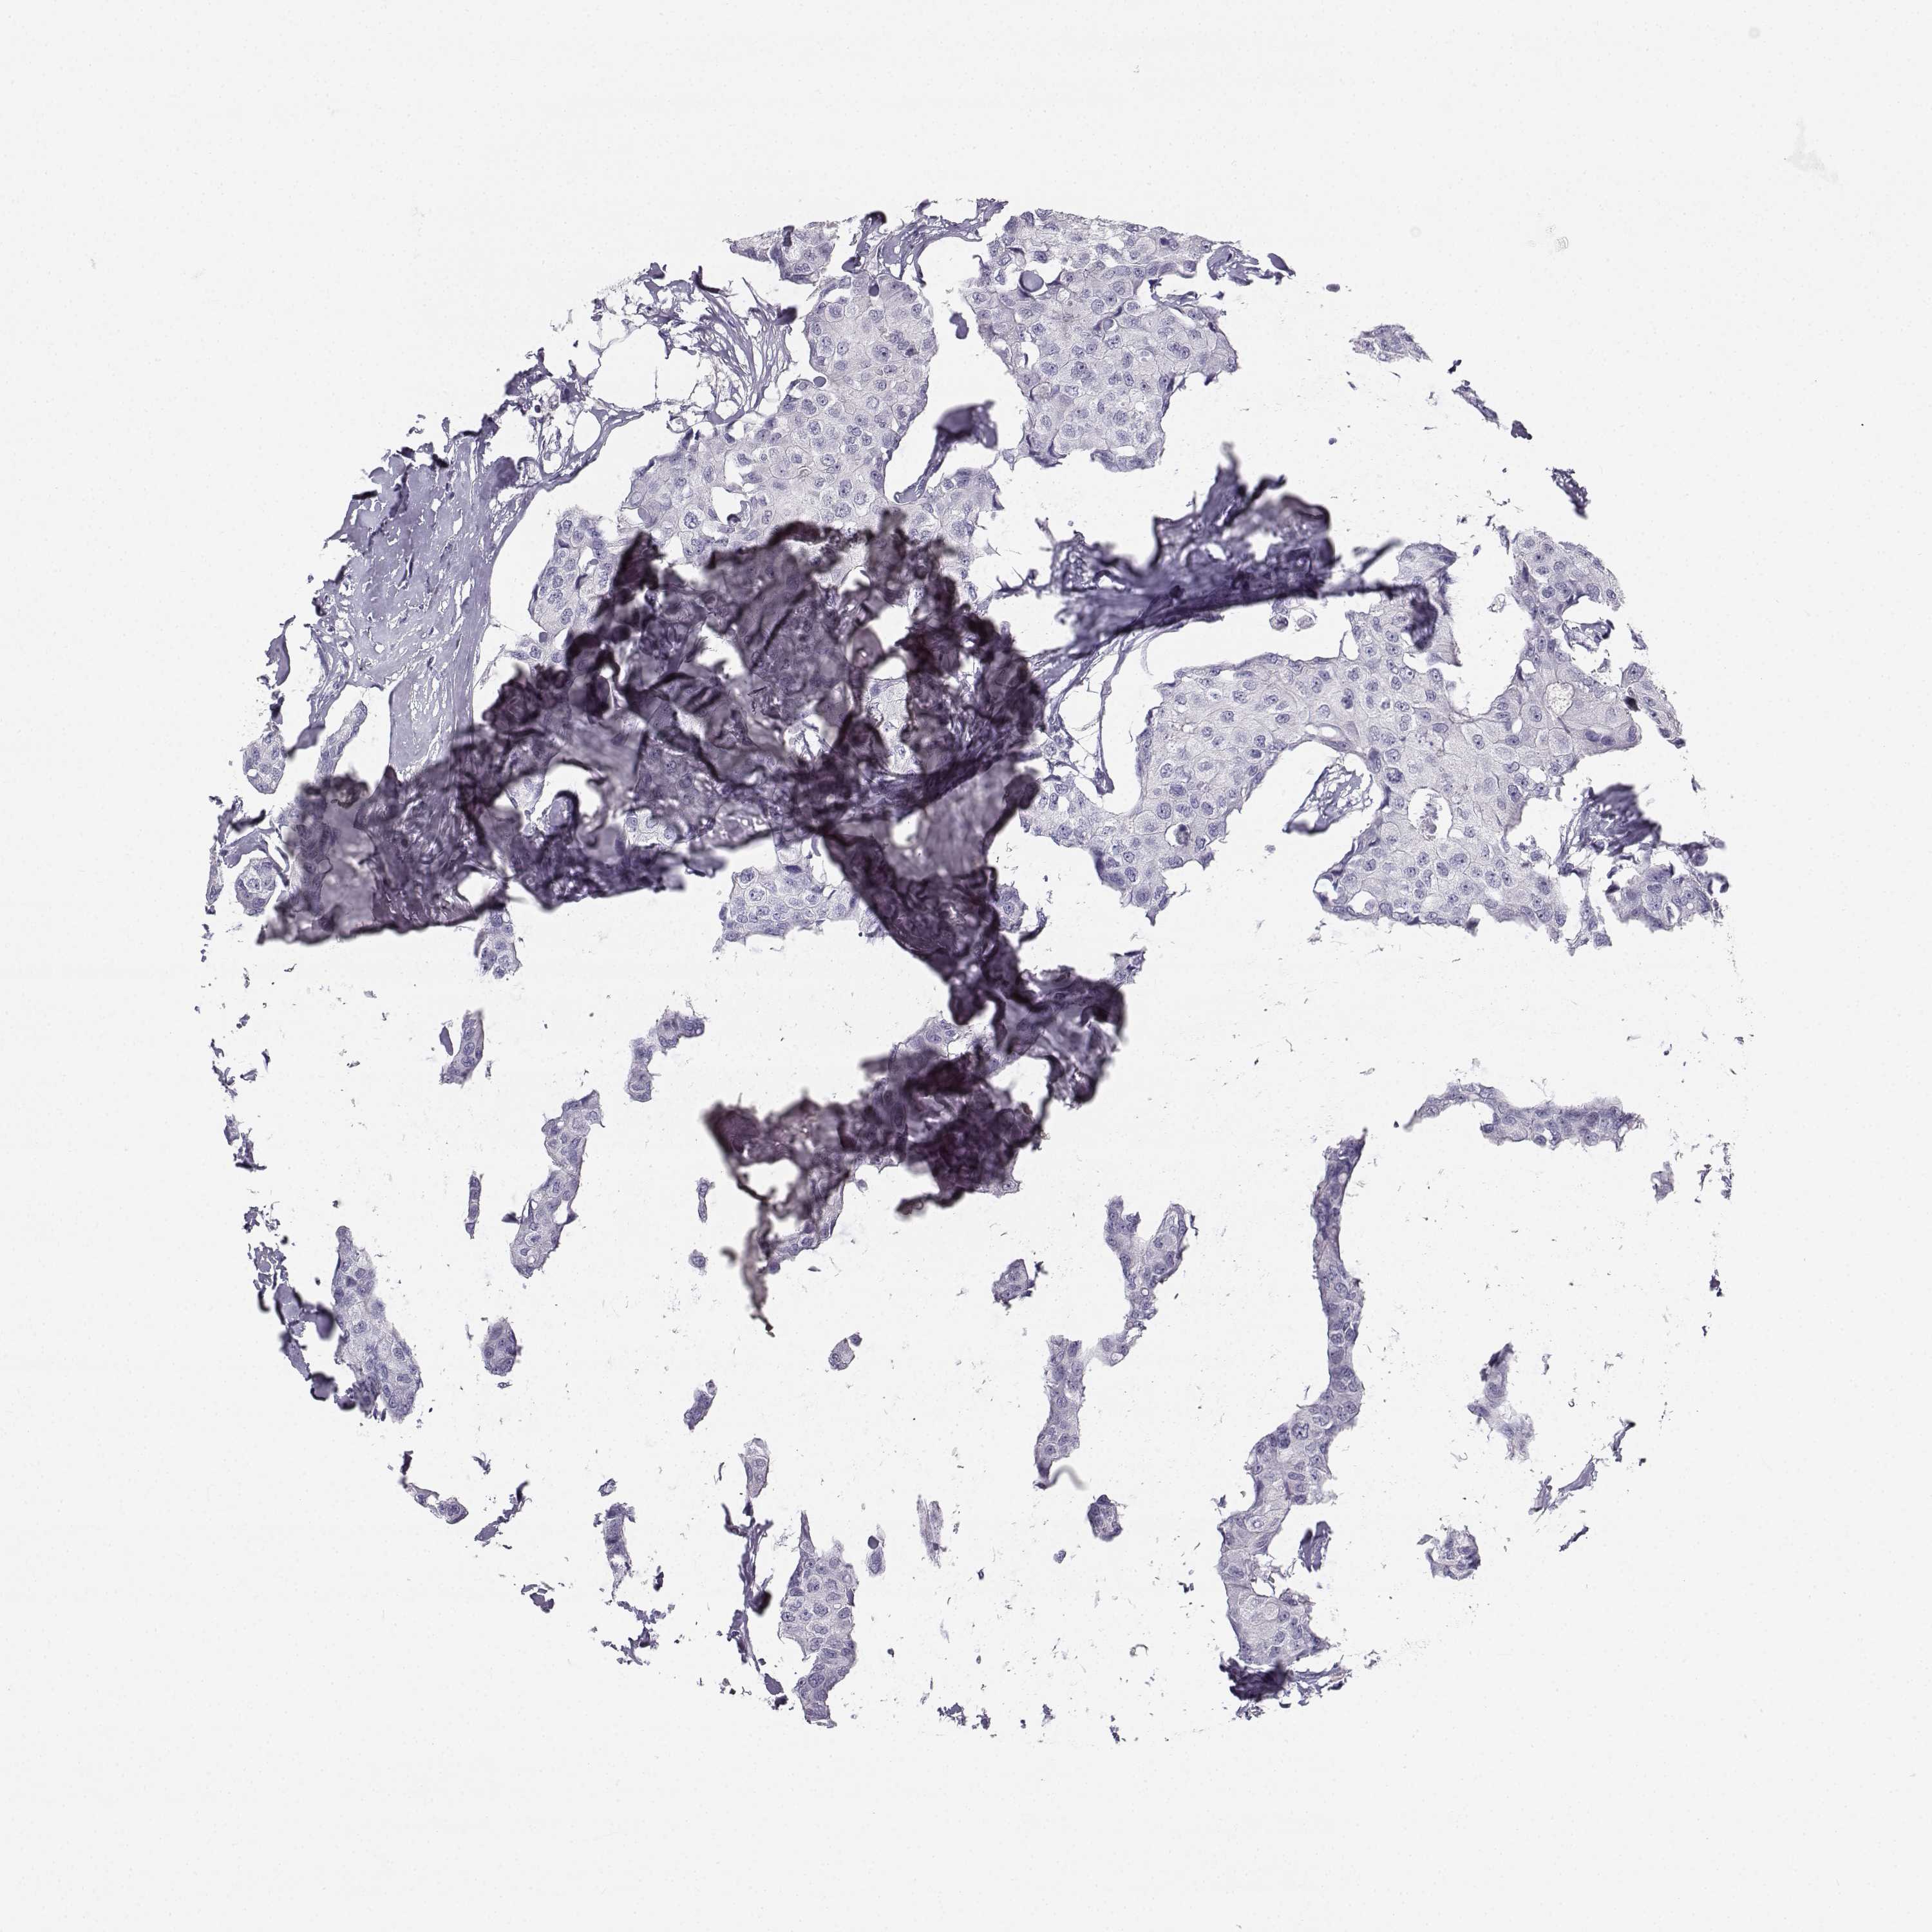

CANCER BREAST CANCER Show tissue menu

BRCA TCGA BRCA VALIDATION PROTEIN EXPRESSION